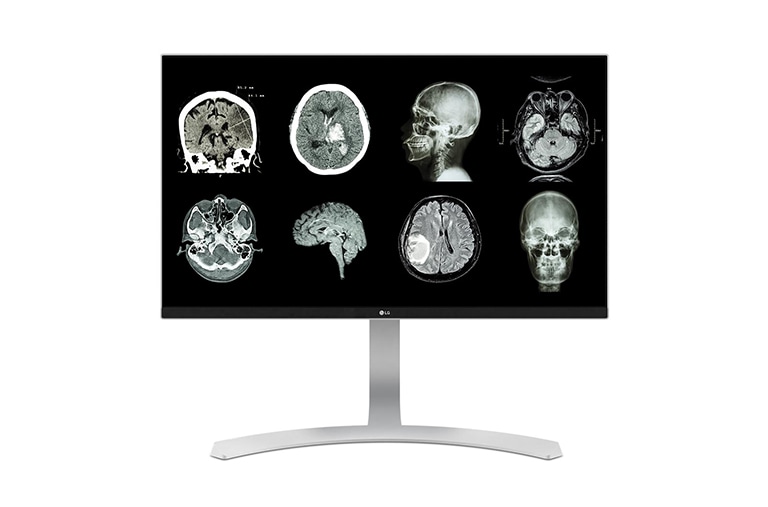

27" 4K & 5K UHD Màn hình y tế